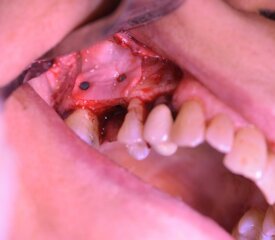

Rialzo del Seno Mascellare